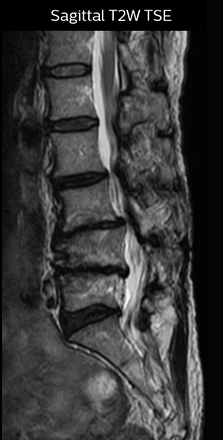

“Before NerveVIEW, diagnosis by MRI alone was sometimes difficult, unless there was a strong suspicion based on clinical symptoms,” says Shoji Yabuki, MD, DMSc, Orthopedic surgeon at Fukushima Medical University School of Medicine. “This is why we routinely perform selective lumbosacral radiculography (nerve root block) and x-ray in such cases. However, radiculography can only depict nerves as far as the contrast agent reaches. When a nerve is distorted by compression, the contrast agent will not pass through this compressed area, preventing us from evaluating the full nerve compression.”

“For example, in sagittal images, when the presence of fat is observed in the intervertebral foramen, it suggests that there is a margin around the nerve. Similarly, the absence of fat indicates that the nerve is being compressed. So, we used to deduce nerve compression indirectly. With NerveVIEW, however, we can observe the condition of the nerves directly, regardless of the presence or absence of fat. We always prefer such direct observation of anatomy over having to make an inference about it.”

“The intra-luminal signal of veins, especially around the intervertebral space, can be suppressed well with NerveVIEW. As a result, we can easily observe the detailed nerve structure around the posterior ganglion,” he says. “This is why we use 3D NerveVIEW for intraforaminal stenosis and extraforaminal stenosis/herniation (lateral disc herniation). On the other hand, if herniation is suspected to exist inside the dorsal root ganglion (DRG), balanced TFE or ProSet-FFE is applied. NerveVIEW is not suitable for evaluating the median type of herniation.” The SE-EPI DWI-based method for MR neurography works well for large FOV exams like whole-body MRI, but focal examination of nerves is often limited by the attainable spatial resolution (both inplane and slice direction) and geometric distortion. “3D NerveVIEW achieves higher in-plane resolution – close to our other routine spine sequences – and the source images can be used instead of adding a fat-suppressed T2-weighted sequence,” Tanji says.